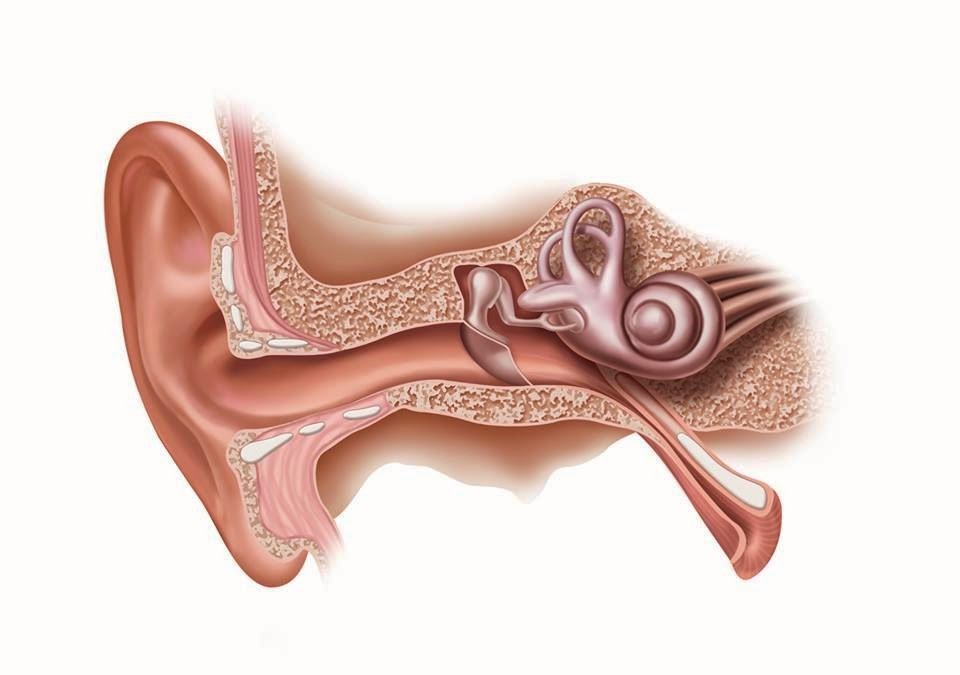

Современные слуховые аппараты при сенсоневральной тугоухости